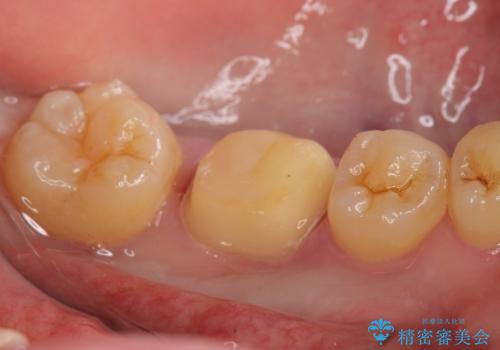

- 左下6の歯が欠けてしまったので診て欲しいといらっしゃった方の症例です。

虫歯除去後、オールセラミッククラウンによる補綴を行いました。